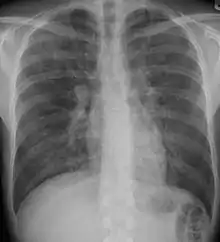

| End-stage pulmonary fibrosis of unknown origin, taken from an autopsy | |

X-rays

Chest radiography is usually the first test to detect interstitial lung diseases, but the chest radiograph can be normal in up to 10% of patients, especially early in the disease process.[12][13]

High resolution CT of the chest is the preferred modality, and differs from routine CT of the chest. Conventional (regular) CT chest examines 7–10 mm slices obtained at 10 mm intervals; high resolution CT examines 1–1.5 mm slices at 10 mm intervals using a high spatial frequency reconstruction algorithm. The HRCT therefore provides approximately 10 times more resolution than the conventional CT chest, allowing the HRCT to elicit details that cannot otherwise be visualized.[12][14]

Radiologic appearance alone however is not adequate and should be interpreted in the clinical context, keeping in mind the temporal profile of the disease process.[12]